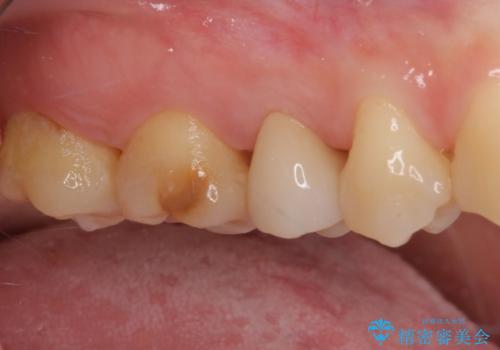

神経が死んで変色した歯 根管治療とオールセラミッククラウン

- 近医にて右上奥歯に大きなむし歯があると指摘されたとのことで来院された患者様です。

診査の結果、既に歯の神経は失活して変色しておりましたが、特に痛みは認めませんでした。

根管治療を行った後にオールセラミッククラウンにて補綴することとしました。